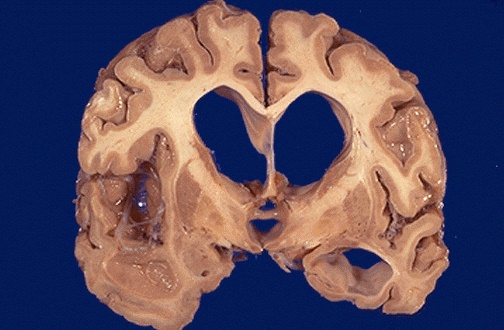

Note the marked dilation of the cerebral ventricles. This is hydrocephalus. Hydrocephalus can be due to lack of absorption of CSF or due to an obstruction to flow of CSF. Hydrocephalus can be a long-term complication of infection. A basilar meningitis, for example, may lead to scarring that obstructs CSF outflow via the foramina of Luschka or Magendie. Inflammation with scarring of arachnoid granulations at the vertex may diminish CSF absorbtion. |